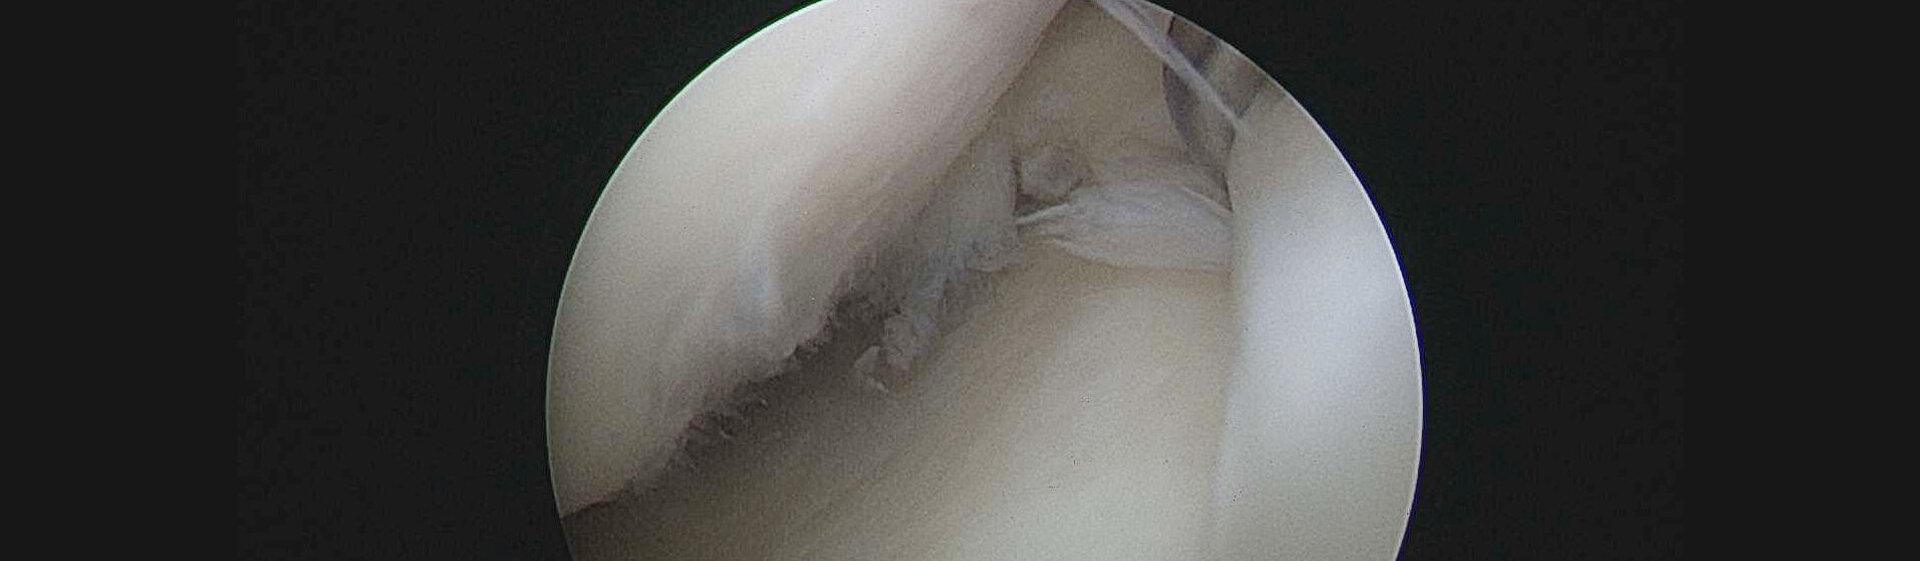

Knorpel ist ein Gewebe ohne Durchblutung, das sich nicht neu bilden kann. Aber durch spezielle Techniken kann die Bildung von Ersatzgewebe gefördert werden, z. B. durch Mikrofrakturierung. Außerdem nutzen wir eine moderne Kollagenmatrix, die auf Defekte aufgebracht wird und so die Bildung von Ersatzgewebe anregt.

Der Ersatz kann auch durch Knorpel-Knochenzylinder aus gesunden Gelenkanteilen erfolgen. Die Methode wird gewählt nach Defektgröße und Alter des Patienten.